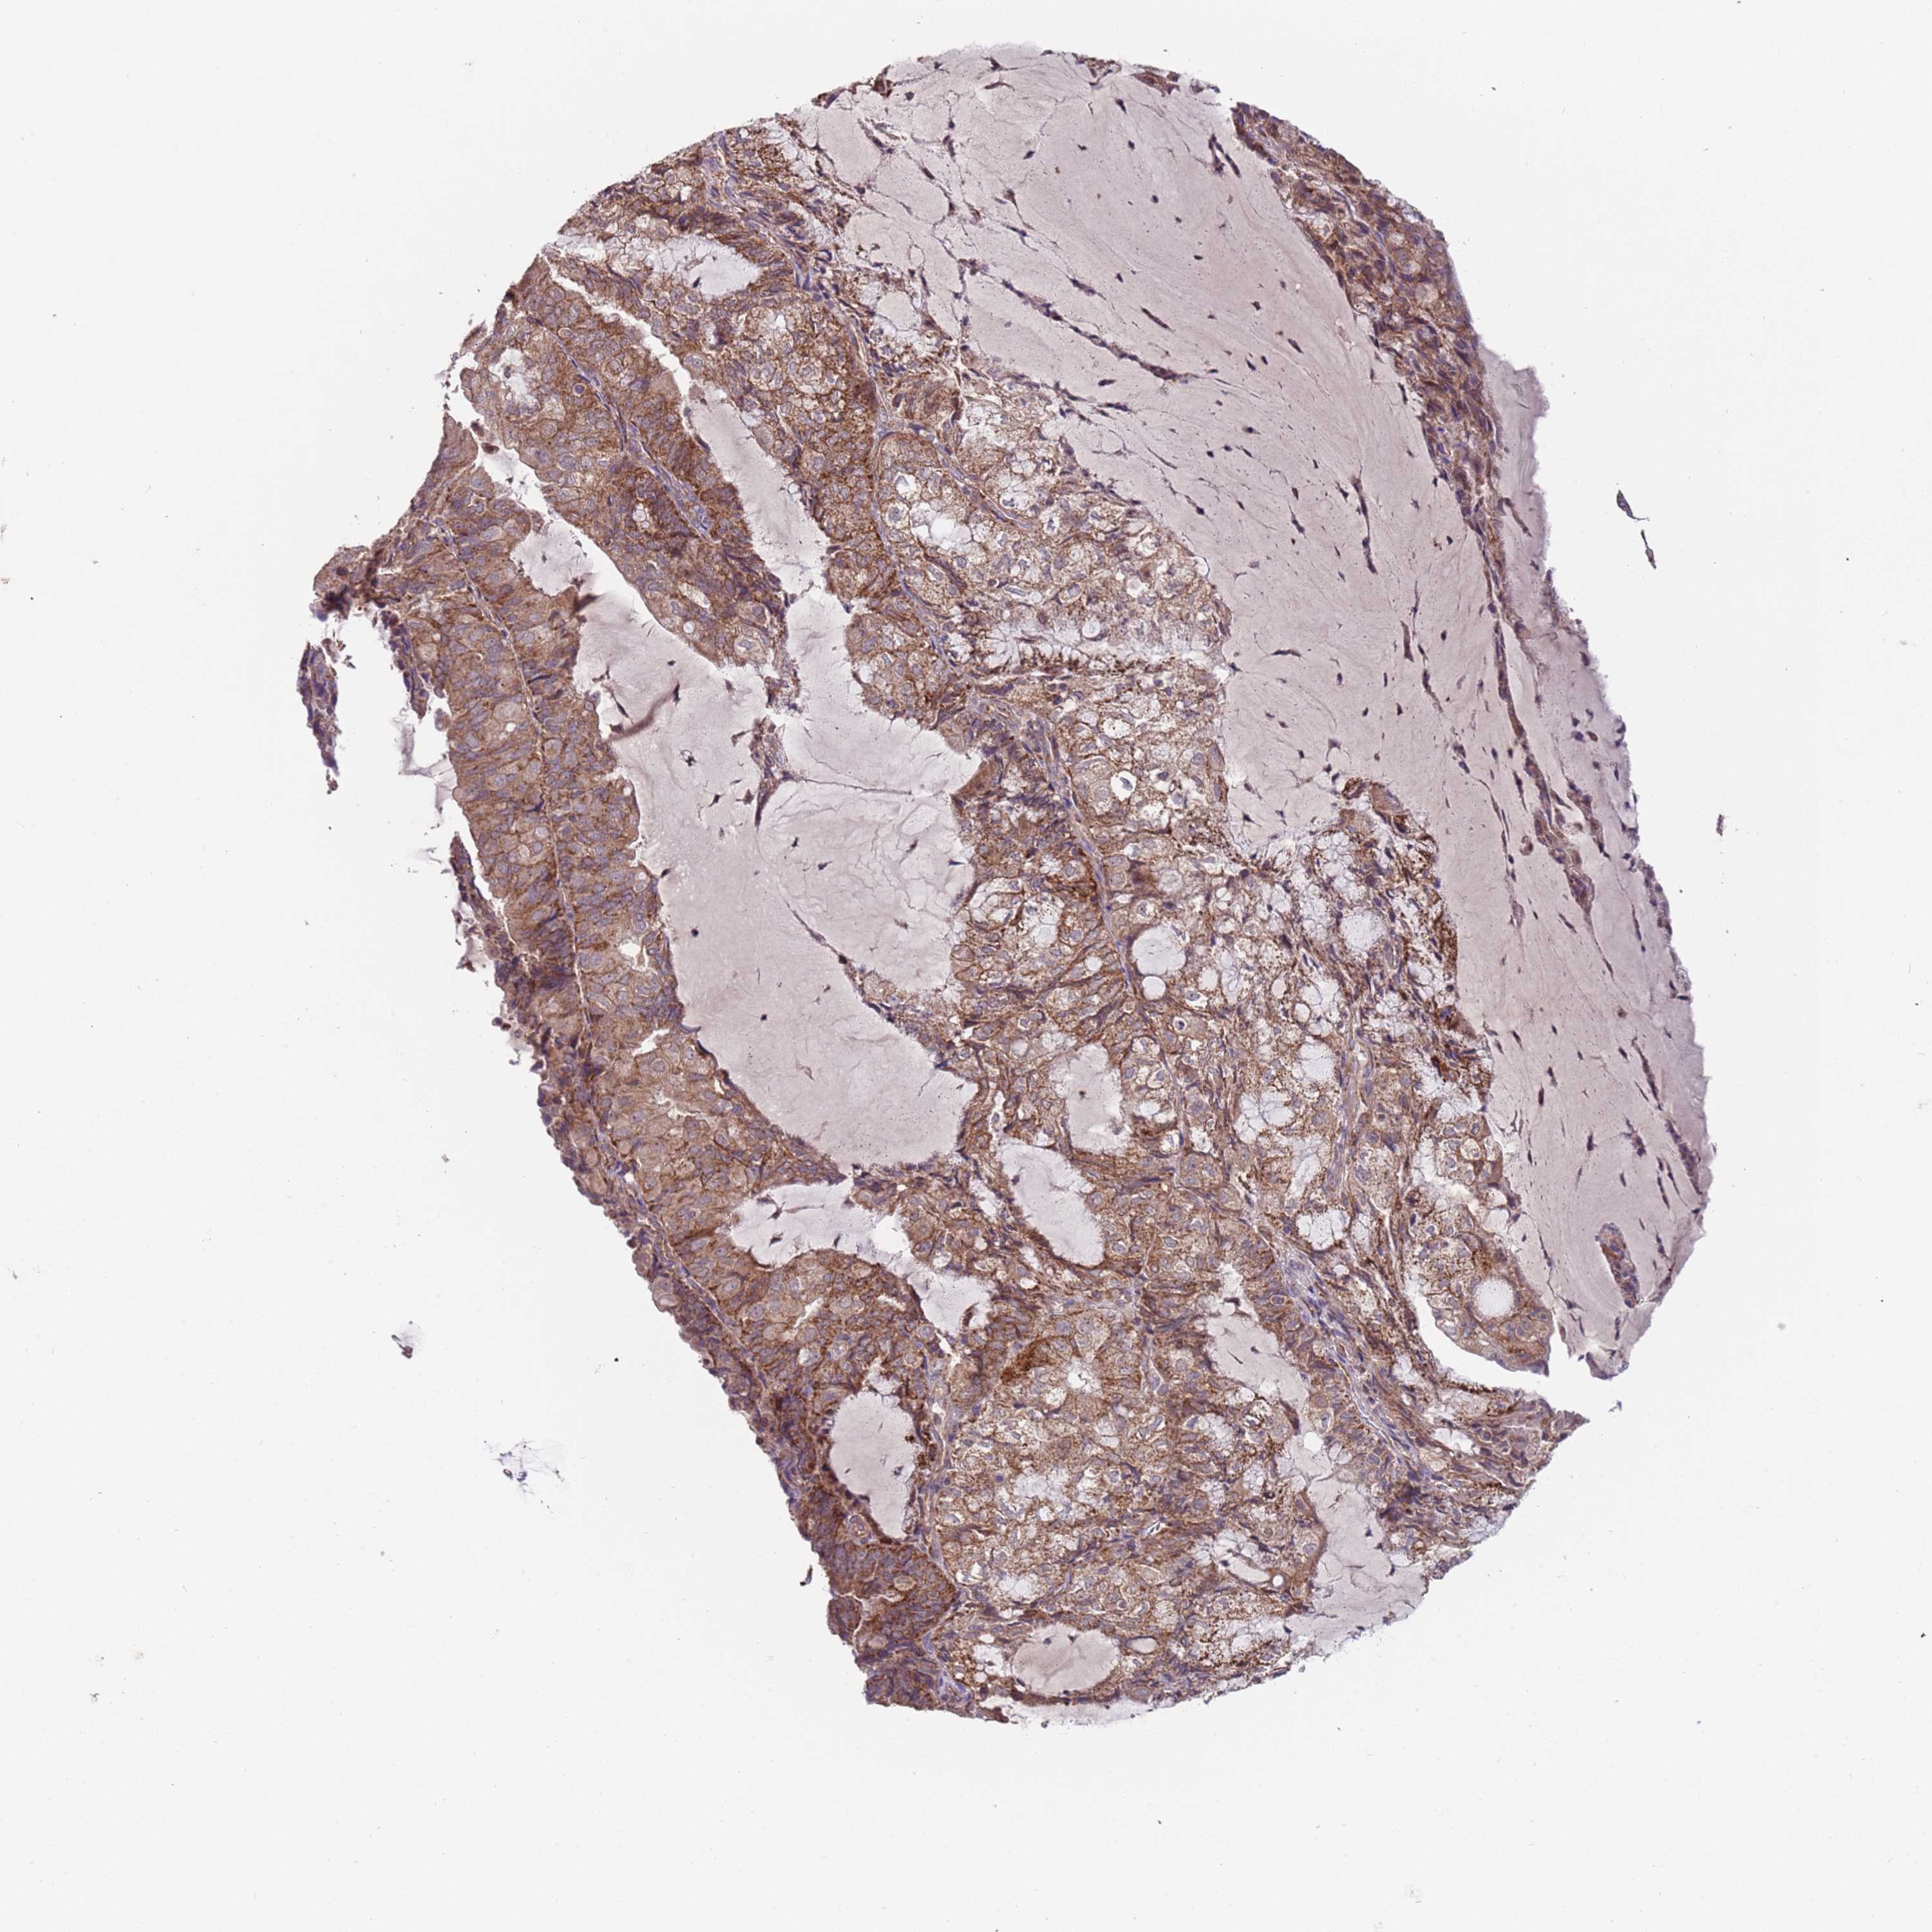

ENDOMETRIAL CANCER - Protein expressioni

A mouse-over function shows sample information and annotation data. Click on an image to view it in a full screen mode. Samples can be filtered based on level of antibody staining by selecting one or several of the following categories: high, medium, low and not detected. The assay and annotation is described here.

Note that samples used for immunohistochemistry by the Human Protein Atlas do not correspond to samples in the TCGA dataset.

Antibody stainingi

Antibody staining in the annotated cell types in the current human tissue is reported as not detected, low, medium, or high, based on conventional immunohistochemistry profiling in selected tissues. This score is based on the combination of the staining intensity and fraction of stained cells.

Each image is clickable and will lead to virtual microscopy that enables deeper exploration of all samples and also displays staining intensity scores, fraction scores and subcellular localization as well as patient and tissue information for each sample.

Antibody HPA040689

Antibody HPA043903

Staining

High

Medium

Low

Not detected

Intensity

Strong

Moderate

Weak

Negative

Quantity

>75%

75%-25%

<25%

None

Location

Nuclear

Cytoplasmic/membranous

Cytoplasmic/membranous,nuclear

Adenocarcinoma, NOS